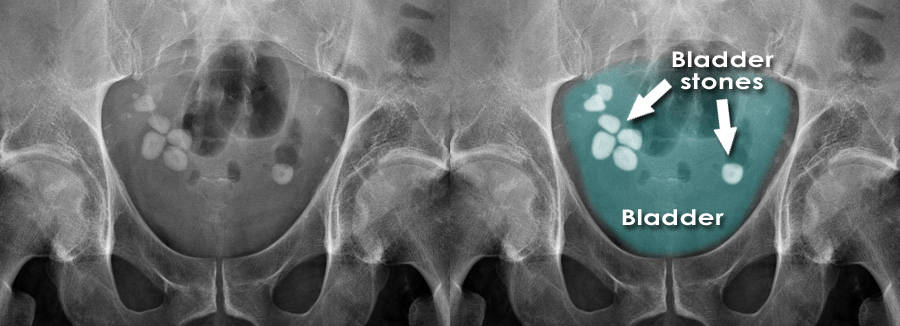

Foto Polos Abdomen (KUB)

Foto polos ginjal-ureter-kandung kemih (kidney-ureter-bladder/KUB) dapat membantu mengidentifikasi batu dan radiopasitasnya, serta berguna untuk perencanaan terapi dan follow-up. Sensitivitas foto KUB berkisar 21-78% untuk batu kandung kemih yang terdeteksi sistoskopi. Batu yang lebih besar lebih mungkin bersifat radiopak, namun komposisi batu sangat mempengaruhi tampilan radiografi. Batu kalsium oksalat dan kalsium fosfat umumnya radiopak, sementara batu asam urat murni dan beberapa batu campuran bersifat radiolusen.